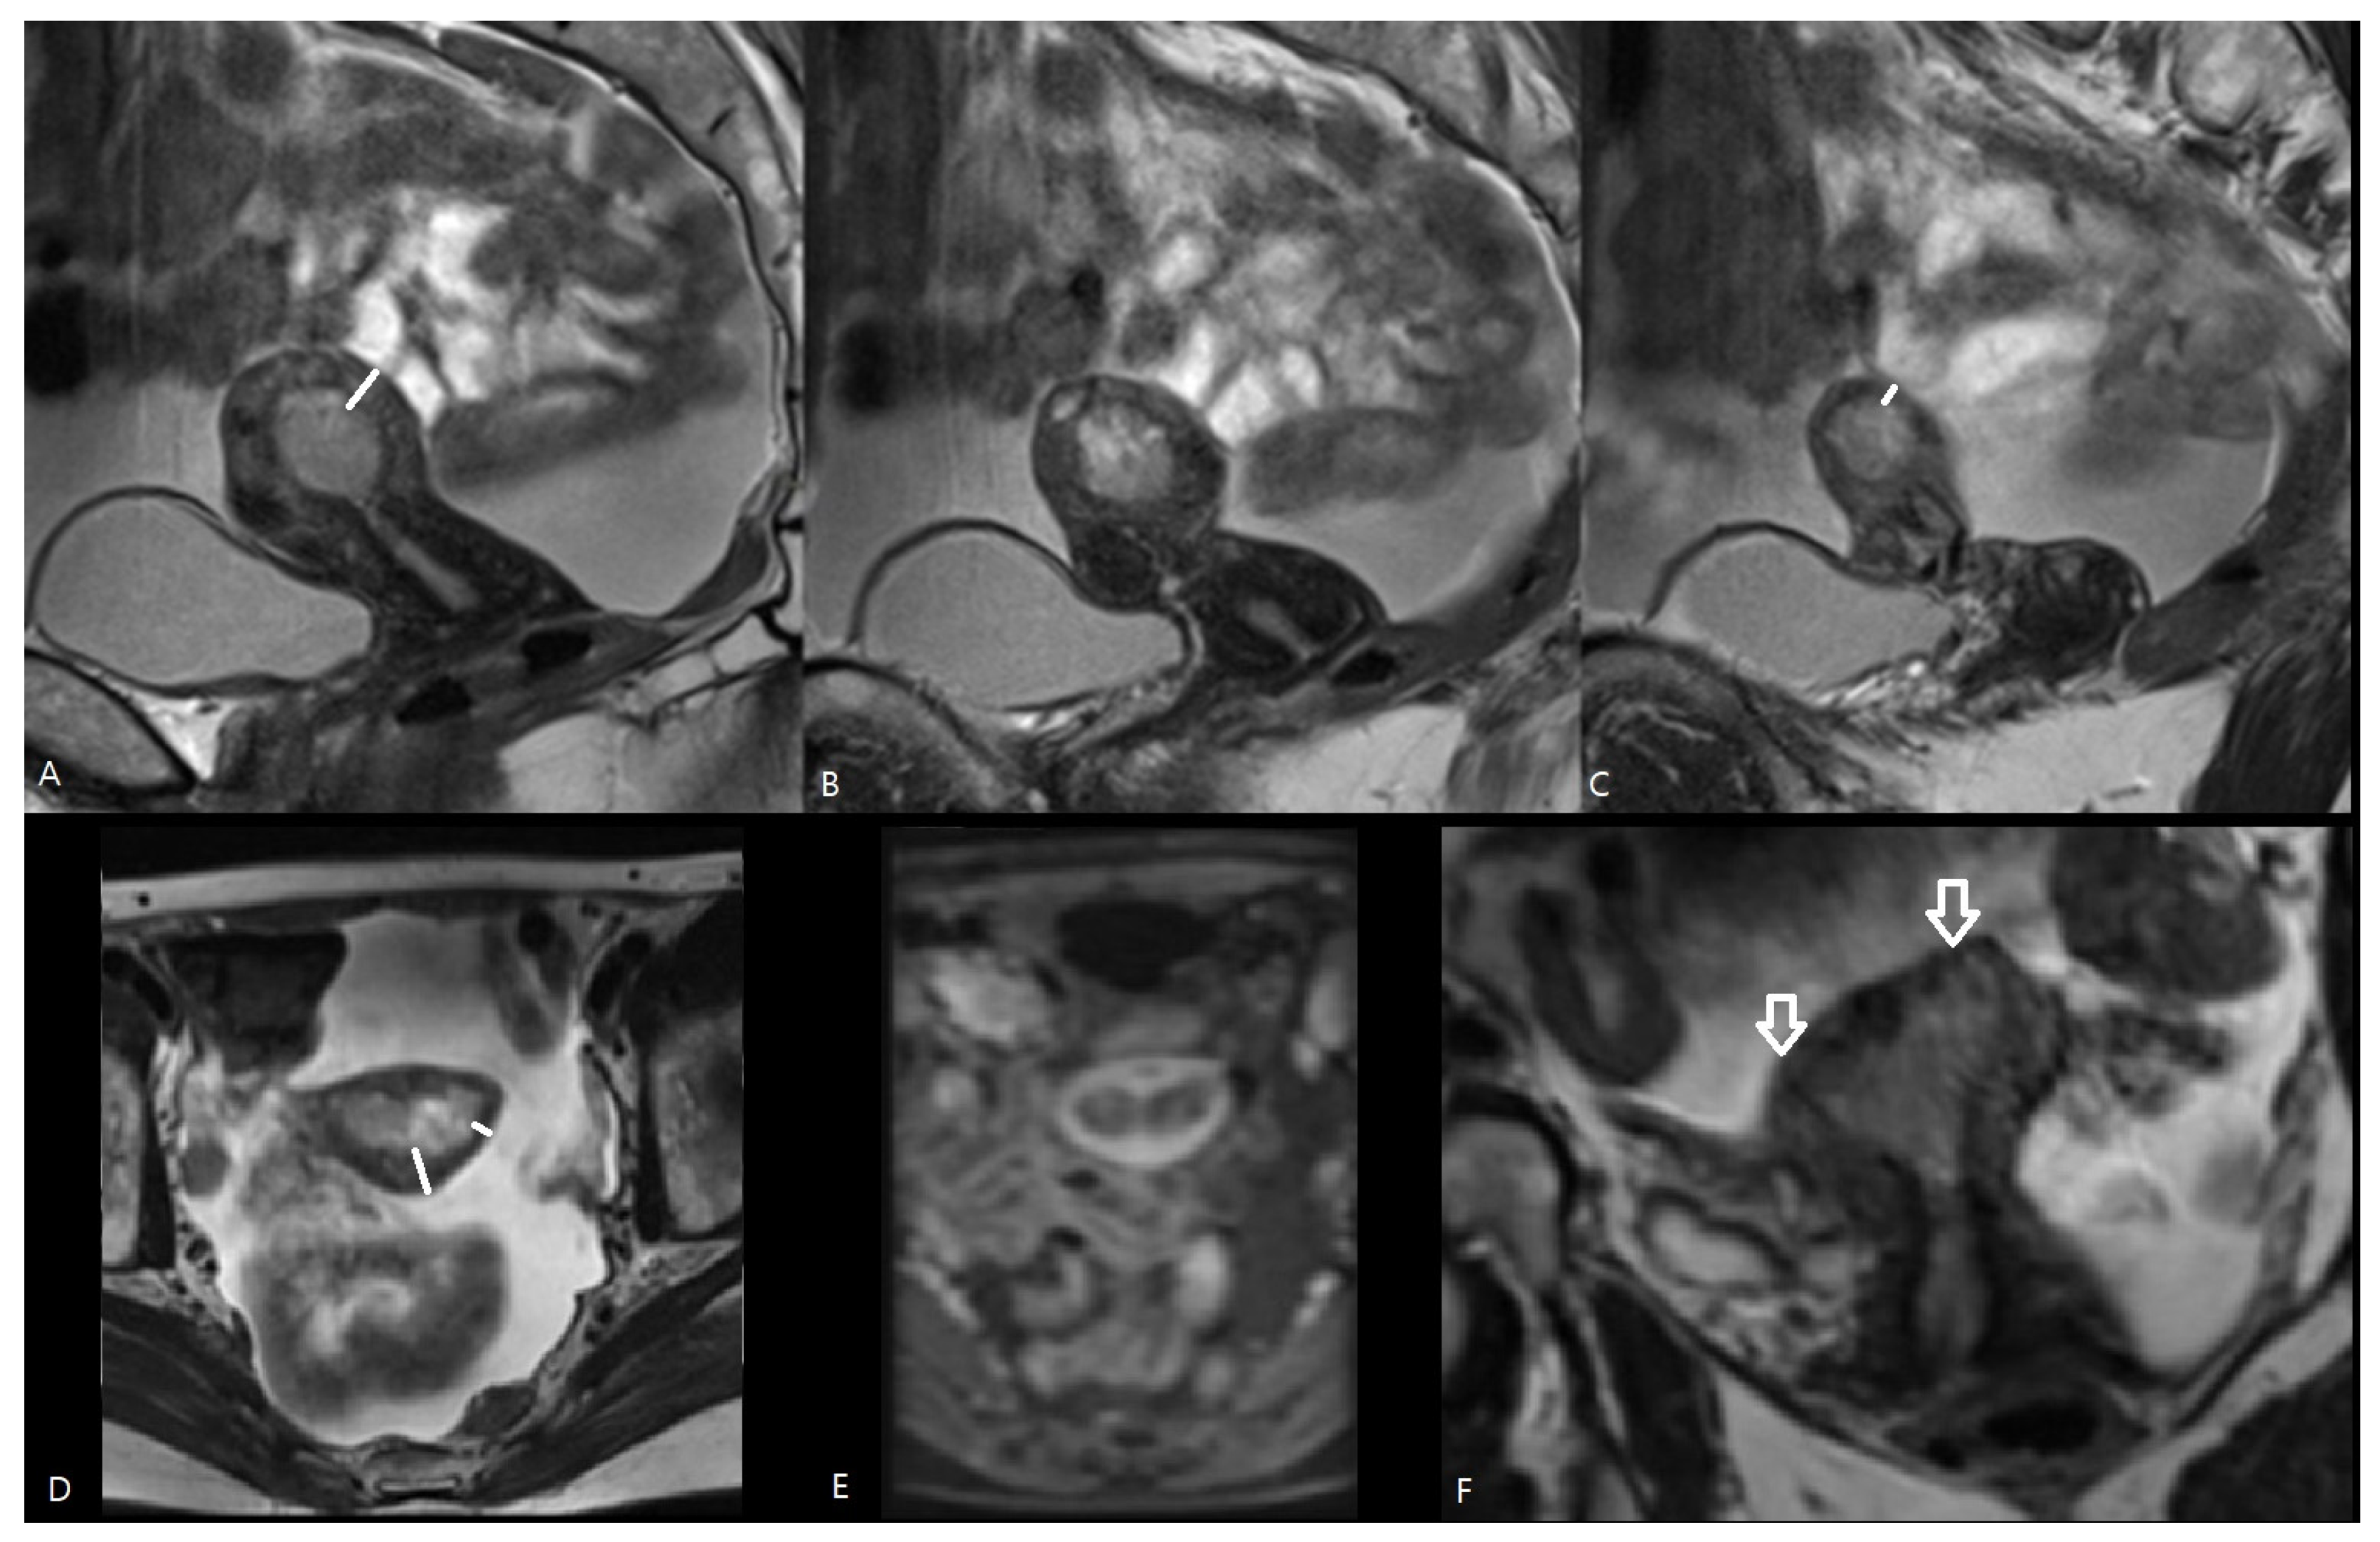

Hashimoto et al. [15] reported that preoperative MRI-based cancer stages and postoperative histopathological cancer stages were concordant in 70.0% of patients. The EC stage was underdiagnosed in MRI in 21.7% and overstaged in 8.2% of patients. This larger risk of understaging than overstaging with MRI was also observed in our study: the MRI-based T-stage was identical to the pathological T-stage in 57.1%, but the EC stage was underdiagnosed via MRI in 28.6% of patients and overstaged in 14.2% of patients. There are several causes reducing the accuracy of MRI in the local staging of EC. First, estimation of the depth of myometrial invasion is often difficult using MRI as the uterus grows atrophic in postmenopausal patients with an ill-defined junctional zone, hampering measurement of myometrial depth invasion. Moreover, in case of large or polypoid EC, or in the presence of concomitant leiomyomas or adenomyosis, myometrial compression by mass effect may further reduce the tumor-to-myometrium contrast, hampering image interpretation [8,11]. A polypoid EC bulging into the endocervical canal may be mistaken for a cervical stromal invasion, or an EC located intracavitary in the cornu may resemble tumor invasion in the outer half of the myometrium (Figure 3 and Figure 4).

Figure 3.

MRI of endometrial cancer. Sagittal T2-WI (A–C), axial T2-WI (D), axial T1-WI after Gadolinium administration (E) and coronal T2-WI (F). The tumor is extending intraluminal into the left and right cornu (white arrows on (F)). In the cornua, the myometrium is anatomically thinner (short white line in (C,D)) than in the uterine corpus (long white line in (A,D)), which may result in overstaging because intracavitary growth in the cornu (pT1a) may mimic tumor invasion in the outer half of the myometrium (iT1b).